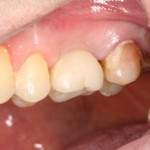

которая через три месяца, к моменту интеграции импланта, выглядит совсем иначе:

Ну и… к моменту установки постоянной коронки, у нас сохранился естественный контур прилегающей десны.

Что, собственно, нам и требовалось сделать.